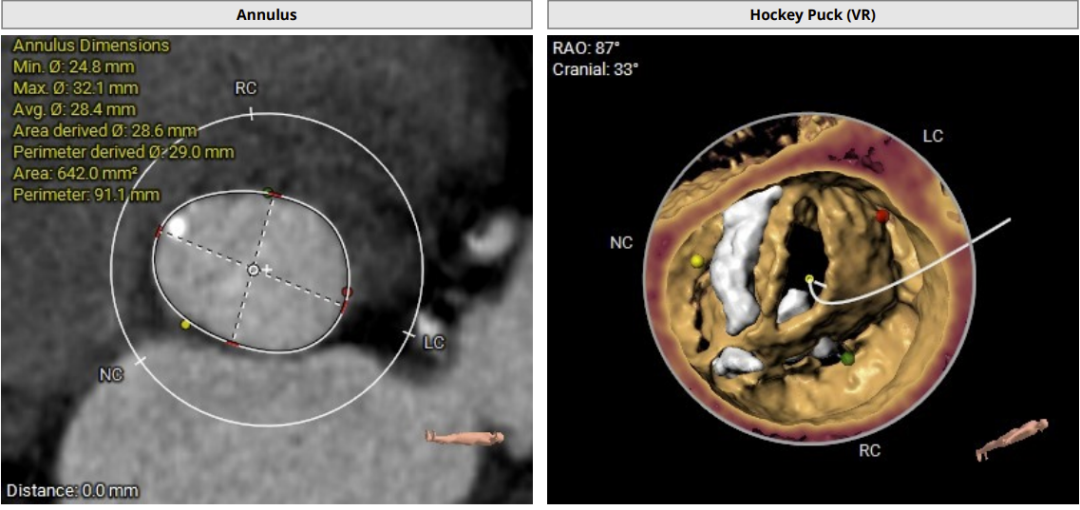

术前CT评估:

CT分析提示:TypeI型二叶瓣,左右瓣叶融合,瓣叶增厚,重度偏心性钙化,钙化位于无冠瓣叶及右无瓣叶交界处,且钙化延伸至LVOT2.5mm,舒张期可见瓣叶关闭不全间隙,右冠高度可,左冠开口平面可见瓣叶,左冠堵塞风险极高,心室略大,室壁厚度可,非横位心,升主动脉瘤样扩张,大血管走行自然,右侧髂总动脉血管细小。

瓣环直径29mm,LVOT直径31.1mm,typeI型瓣叶且偏心钙化位于无冠窦,按照常规瓣膜型号选择标准,但考虑患者两叶瓣,且左冠状动脉阻塞风险极高,downsize选择瓣膜型号,拟植入26mmVenus-A,备29mmVenus-A,高位释放,采用可回收输送系统,术中22mm球囊预扩张sizing后确定最终瓣膜型号选择。左冠预置支架保护。以左侧股动脉为主入路。